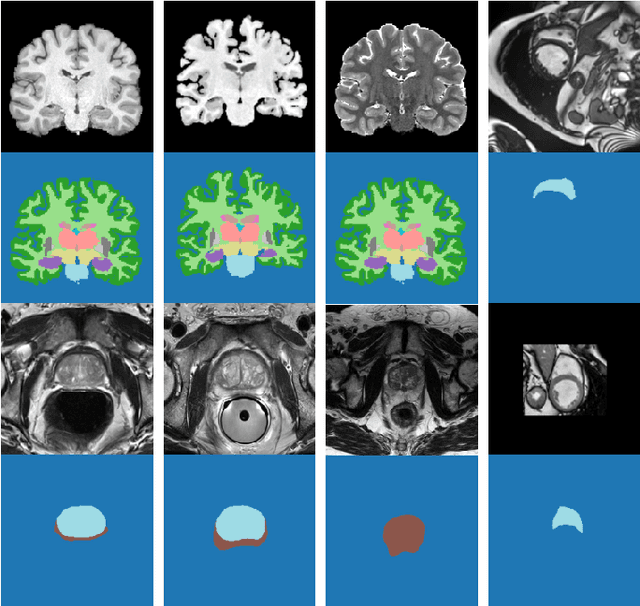

Abstract:Supervised learning-based segmentation methods typically require a large number of annotated training data to generalize well at test time. In medical applications, curating such datasets is not a favourable option because acquiring a large number of annotated samples from experts is time-consuming and expensive. Consequently, numerous methods have been proposed in the literature for learning with limited annotated examples. Unfortunately, the proposed approaches in the literature have not yet yielded significant gains over random data augmentation for image segmentation, where random augmentations themselves do not yield high accuracy. In this work, we propose a novel task-driven data augmentation method for learning with limited labeled data where the synthetic data generator, is optimized for the segmentation task. The generator of the proposed method models intensity and shape variations using two sets of transformations, as additive intensity transformations and deformation fields. Both transformations are optimized using labeled as well as unlabeled examples in a semi-supervised framework. Our experiments on three medical datasets, namely cardic, prostate and pancreas, show that the proposed approach significantly outperforms standard augmentation and semi-supervised approaches for image segmentation in the limited annotation setting. The code is made publicly available at https://github.com/krishnabits001/task$\_$driven$\_$data$\_$augmentation.

Abstract:Supervised deep learning methods for segmentation require large amounts of labelled training data, without which they are prone to overfitting, not generalizing well to unseen images. In practice, obtaining a large number of annotations from clinical experts is expensive and time-consuming. One way to address scarcity of annotated examples is data augmentation using random spatial and intensity transformations. Recently, it has been proposed to use generative models to synthesize realistic training examples, complementing the random augmentation. So far, these methods have yielded limited gains over the random augmentation. However, there is potential to improve the approach by (i) explicitly modeling deformation fields (non-affine spatial transformation) and intensity transformations and (ii) leveraging unlabelled data during the generative process. With this motivation, we propose a novel task-driven data augmentation method where to synthesize new training examples, a generative network explicitly models and applies deformation fields and additive intensity masks on existing labelled data, modeling shape and intensity variations, respectively. Crucially, the generative model is optimized to be conducive to the task, in this case segmentation, and constrained to match the distribution of images observed from labelled and unlabelled samples. Furthermore, explicit modeling of deformation fields allow synthesizing segmentation masks and images in exact correspondence by simply applying the generated transformation to an input image and the corresponding annotation. Our experiments on cardiac magnetic resonance images (MRI) showed that, for the task of segmentation in small training data scenarios, the proposed method substantially outperforms conventional augmentation techniques.